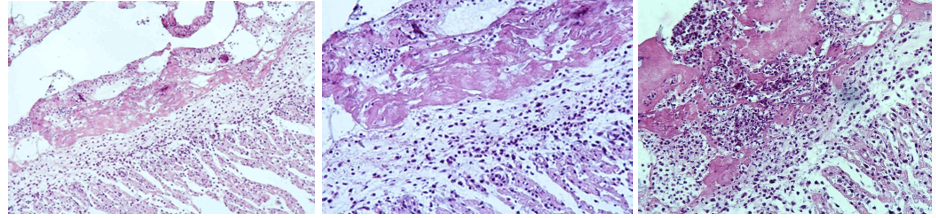

Pleuritis fibrosa (Repair by organization)

Extra note: Importance of this mechanism (repair by organization) is such that the area does not return to normal, but remains in a scarred state, so that the organ or tissue involved is permanently damaged and may be functionally impaired (defect).

Granulation tissue grows into the fibrous exudate to liquify and engulf it (repair process). This pathological process leads to adherence of the parietal and visceral layers. From the bottom: mature fibrous CT → granulation tissue → fibrous exudate (neutrophils) in picture.